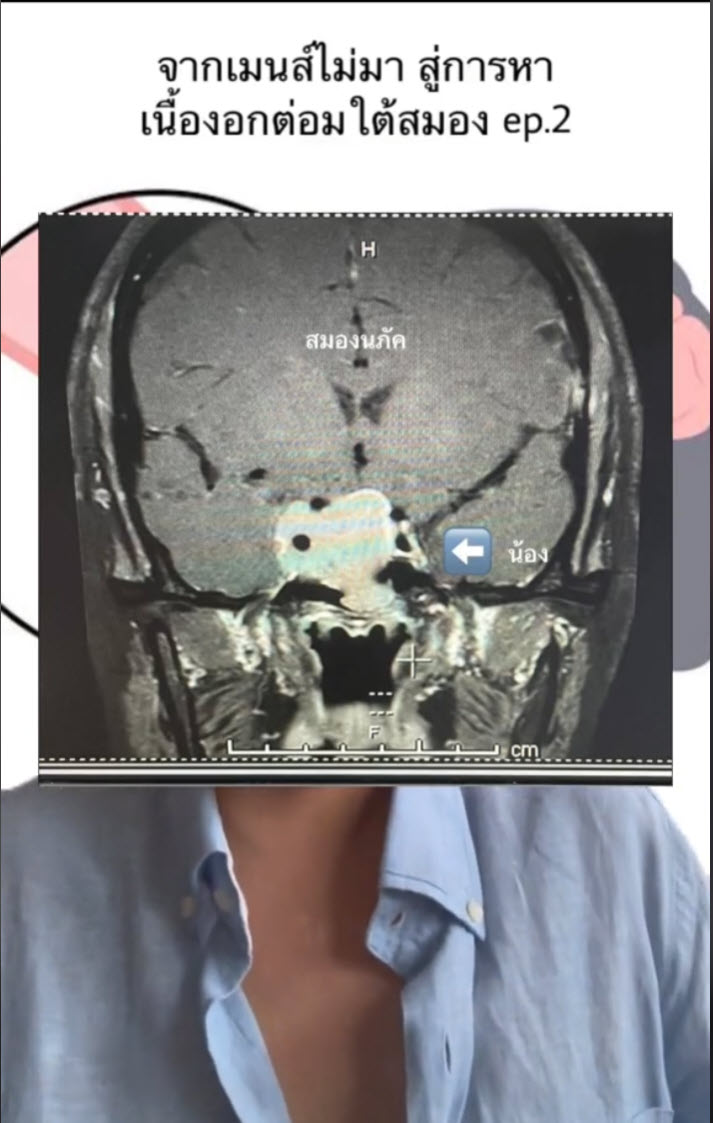

คุณหมอแนะนำให้ทำ MRI เมื่อได้เห็นภาพเอกซเรย์ก็พบความผิดปกติ เหมือนมีก้อนขาว ๆ อยูในกระโหลก จนกระทั่งได้เจอหมอได้แจ้งว่า เจอเนื้องอกต่อมใต้สมอง 3 เซนติเมตร โดยเบื้องต้นพบว่าเนื้องอกนั้นเกิดขึ้นได้โดยไม่ต้องมีสาเหตุ ไม่มีวิธีป้องกัน ซึ่งตอนนี้เธอนั้นเข้าสู่ขั้นตอนการรักษาแล้ว